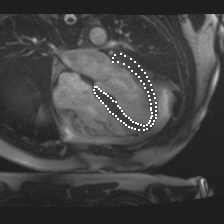

Accurate segmentation and motion estimation of myocardium have always been important in clinic field, which essentially contribute to the downstream diagnosis. However, existing methods cannot always guarantee the shape integrity for myocardium segmentation. In addition, motion estimation requires point correspondence on the myocardium region across different frames. In this paper, we propose a novel end-to-end deep statistic shape model to focus on myocardium segmentation with both shape integrity and boundary correspondence preserving. Specifically, myocardium shapes are represented by a fixed number of points, whose variations are extracted by Principal Component Analysis (PCA). Deep neural network is used to predict the transformation parameters (both affine and deformation), which are then used to warp the mean point cloud to the image domain. Furthermore, a differentiable rendering layer is introduced to incorporate mask supervision into the framework to learn more accurate point clouds. In this way, the proposed method is able to consistently produce anatomically reasonable segmentation mask without post processing. Additionally, the predicted point cloud guarantees boundary correspondence for sequential images, which contributes to the downstream tasks, such as the motion estimation of myocardium. We conduct several experiments to demonstrate the effectiveness of the proposed method on several benchmark datasets.